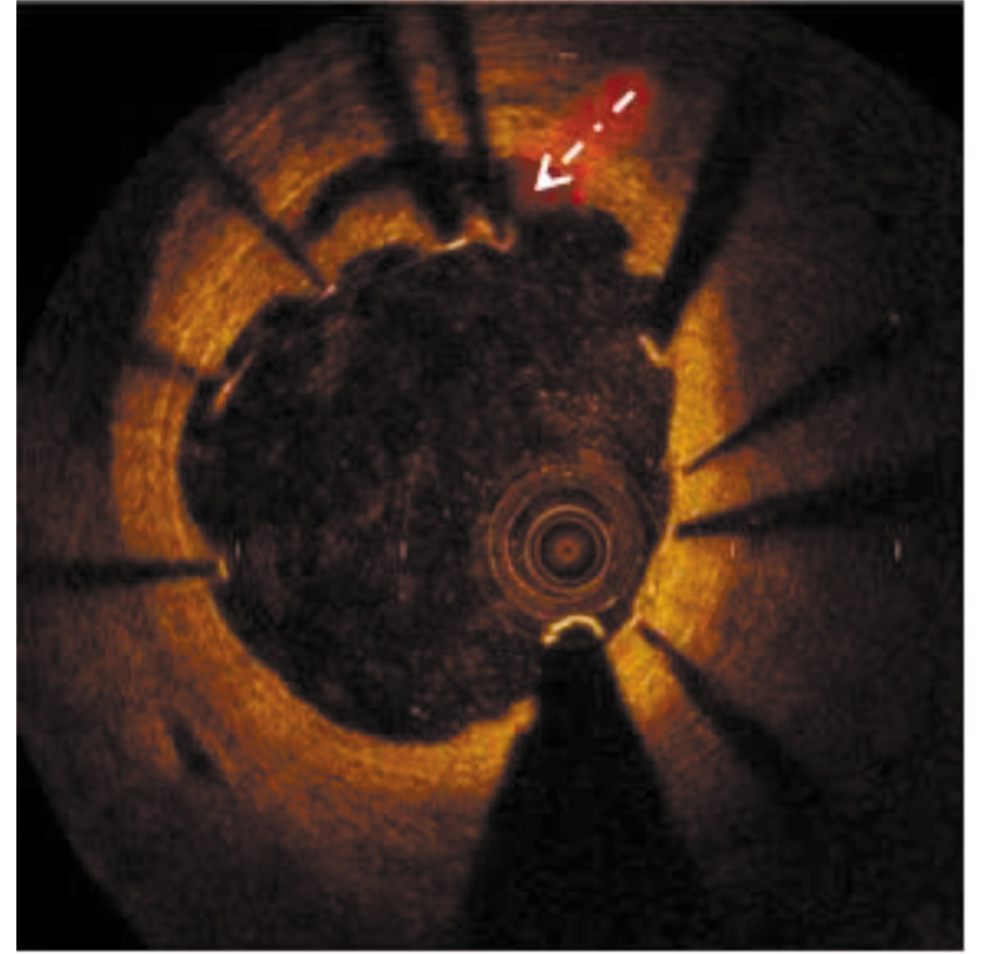

При выполнении ОКТ ПМЖА обнаружены недостаточное прилегание страт в проксимальной и средней части стента и отсутствие его эндотелизации, а также разрыв интимы в приустьевом отделе ПМЖА и протяжённая (>20 мм) субинтимальная гематома, выходящая за пределы области стентирования до бифуркации ПМЖА с ДВ. На всём протяжении ПМЖА визуализировалась трёхслойная структура её стенки без признаков атеросклеротического поражения (рис. 6, 7).

Рис. 6. Изображение оптической когерентной томографии передней межжелудочковой артерии в приустьевом отделе. Стрелкой указаны разрыв интимы с формированием субинтимальной гематомы, а также мальпозиция страт стента.

Fig. 6. Optical coherence tomography image of AIVA in the aortic section. The arrow indicates intimal rupture with formation of subintimal hematoma, as well as malposition of the stent strut.

Рис. 7. Визуализация при оптической когерентной томографии субинтимальной гематомы на уровне средней трети передней межжелудочковой артерии.

Fig. 7. OCT visualization of subintimal hematoma at the level of the middle third of AIVA.